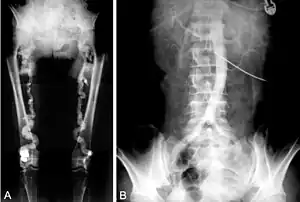

B. Translumbar aortography shows near-total obstruction of the femoral arteries in a patient with Monckeberg's arteriosclerosis.